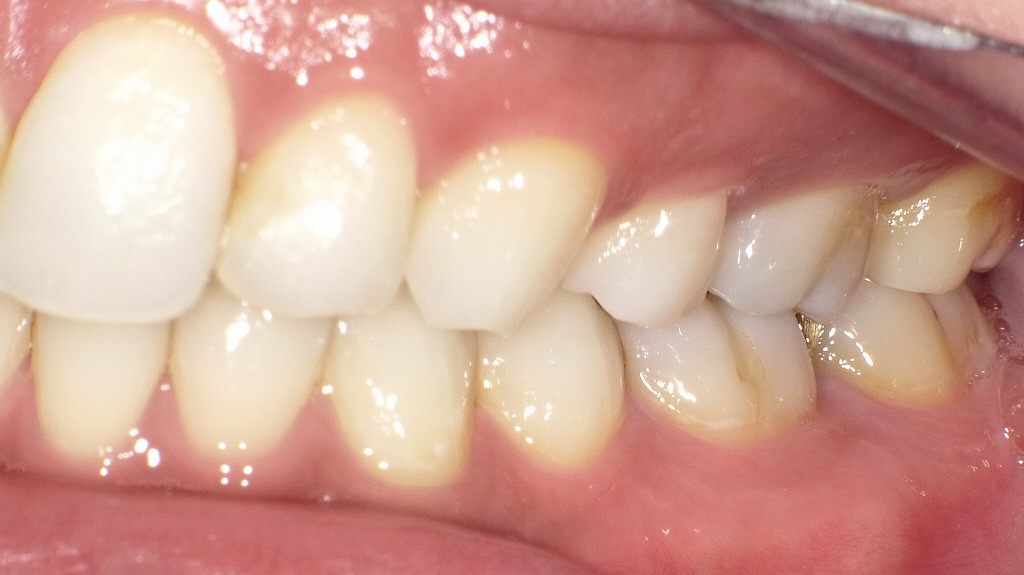

抜歯矯正後の側面観

これらの画像は、抜歯矯正後の側面観を示しています。全体的に咬合関係が良好で、機能的・審美的にもバランスが取れた状態です。

🦷 咬合(かみ合わせ)の特徴

- 上下の犬歯・小臼歯の咬み合わせが理想的で、Class I(正常咬合)に近い関係が確認できます。

- 上顎の歯が下顎の歯を適度に覆っており、オーバーバイト・オーバージェットともに適正範囲内です。

- 前歯から臼歯までスムーズな咬合平面が保たれています。

✨ 歯列と歯軸の整い方

- 上下の歯軸がきれいに整っており、歯列弓が自然なカーブを描いています。

- 上顎前歯の後退により、口元の突出感が改善されています。

- 臼歯部の咬合接触も良好で、咀嚼機能が安定していることがうかがえます。

💬 総合コメント

抜歯矯正により、前歯の位置と奥歯の咬合関係が調和し、理想的な横顔ラインを形成しています。

見た目の美しさだけでなく、噛む力のバランスや機能面でも優れた結果が得られている状態です。